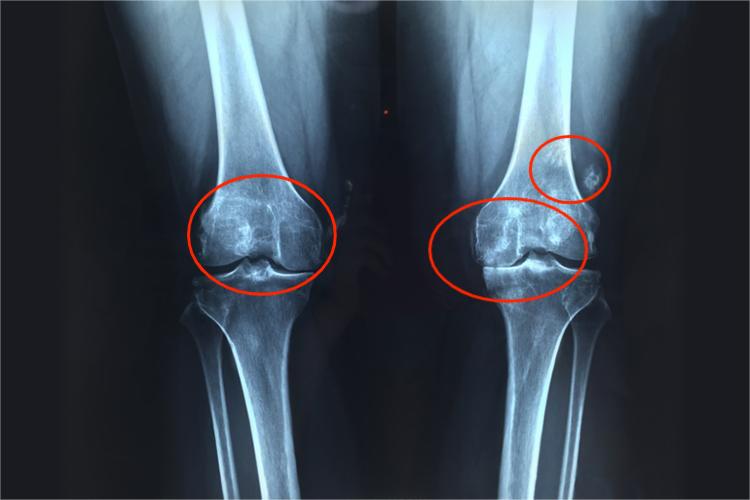

剧烈运动或严重外伤可致半月板撕裂并错位,此时需及时就医,通过MRI等影像学检查明确损伤程度。轻度撕裂可通过关节镜手术进行缝合或修复,术后配合康复训练增强肌肉力量,恢复关节稳定性。